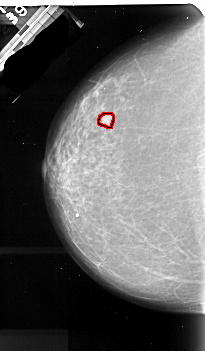

A_1094_1.LEFT_MLO

LEFT_MLO LINES 5536 PIXELS_PER_LINE 3076 BITS_PER_PIXEL 16 RESOLUTION 42 OVERLAY

FILE: A_1094_1.LEFT_MLO.OVERLAY

TOTAL_ABNORMALITIES 1

ABNORMALITY 1

LESION_TYPE MASS SHAPE IRREGULAR MARGINS ILL_DEFINED

ASSESSMENT 4

SUBTLETY 2

PATHOLOGY MALIGNANT

TOTAL_OUTLINES 2

BOUNDARY

CORE